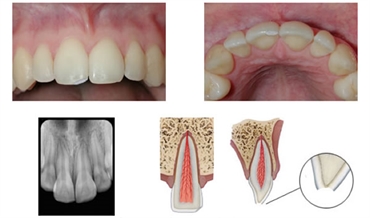

Enamel infraction is characterized by cracks in tooth without the loss of any tooth structure. A patient might not necessarily observe these cracks and usually is detected in routine dental examination. These micro-cracks can be a result of minor trauma. Diagnosis is usually done by a method called transillumination. In this, light rays of specific wavelength are directed on the tooth surface which help in identification of the cracks.

A radiograph of the affected tooth may also be needed. This gives us an indication of whether the tooth has developed any deeper fracture, haemorrhage, inflammation near the tissues, etc. The position of the apex of the root is observed keenly to check for signs of any abnormalities like concussion, intrusion or luxation of the affected tooth.

Treatment usually involves filling up the micro-cracks with a material named composite resin. It is available in two forms: flowable (liquid) and packable (solid). Liquid form of composite resin is usually used to fill up these micro-cracks. In order to apply this composite resin, the affected area us first etched with an acid that leads to the formation of micro-porosities. The flowable resin is then applied, that locks within these micro-porosities. Finally, a light of a specific wavelength is directed to the resin that accelerates its setting.